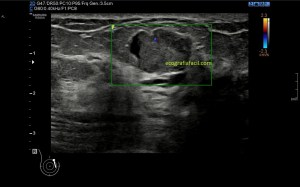

3

Medidas en eje corto.